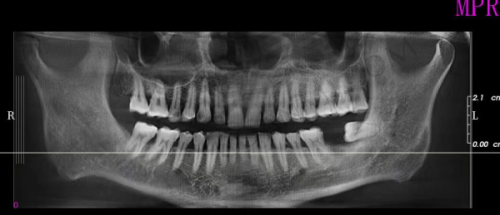

在患者决定进行韩国DIO种植牙手术前,鄂尔多斯中诺口腔的医护人员会为患者进行全方面的口腔检查,包括口腔X光、CT等,以正确了解患者的牙槽骨情况和口腔健康状况。武克奇医生会根据检查结果,与患者进行充分的沟通,制定更适合患者的种植方案,并详细告知患者手术的过程、风险和注意事项。在手术后,医院会为患者提供专精的术后护理指导,包括饮食、口腔清洁等方面的注意事项。医护人员还会定期回访患者,了解患者的修复情况,及时解决患者遇到的问题,确保种植牙的成效和患者的口腔健康。